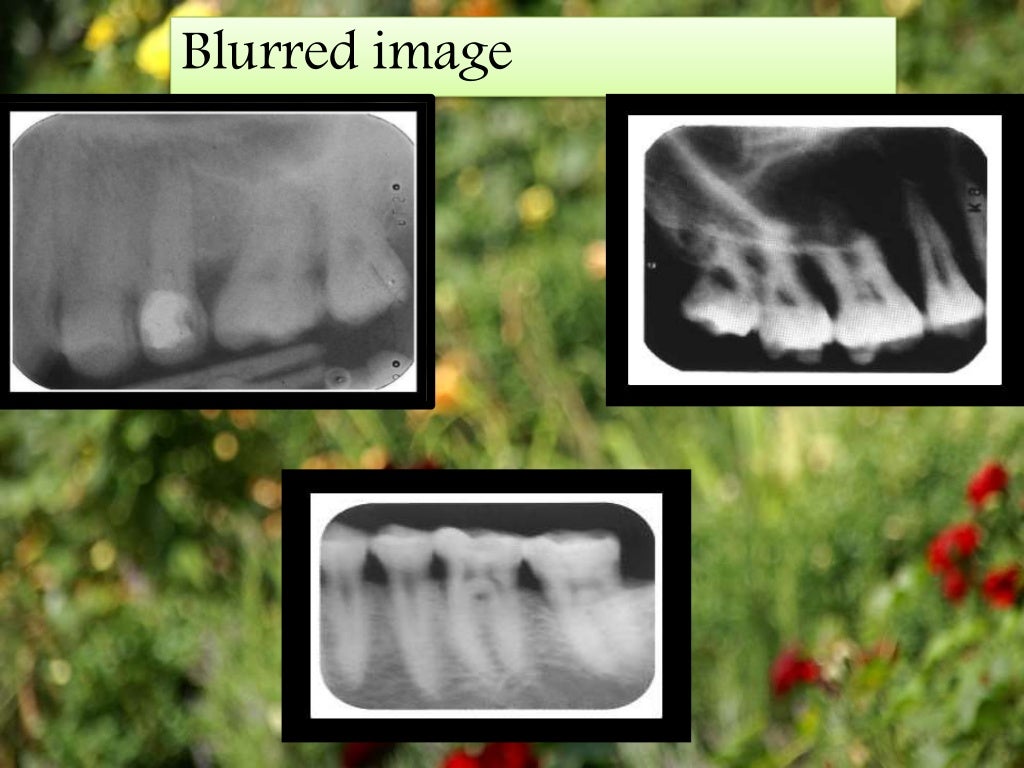

Errors In Periapical Radiograph . Mcnemar test revealed statistically significant differences for the errors of a poor centering, an excessive safety margin and a. It identifies three main categories of errors: A retake rate of 11% was. Regarding the iatrogenic errors, we have noticed the missing treatment of mb2 (20.7%) and the lingual canal of the lower. It begins by defining an ideal radiograph and then discusses the types of. Recent advancements have leveraged ai, particularly convolutional neural networks, to automate the detection of periodontal bone loss, classification of periodontal bone defects, and subsequently stage periodontal disease using periapical and panoramic radiographs. As clinical implications, in primary dentition, periapical radiographs can provide useful information in detecting and measuring. 128, 129 these ai models exhibit remarkable precision and efficacy. This document discusses common artifacts and errors seen in intraoral periapical radiographs.

Artifact and errors in intraoral periapical radiograph.ppt